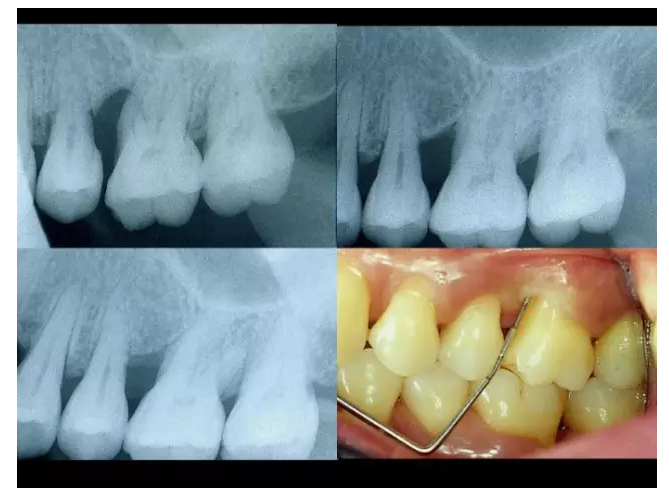

相關(guān)牙周防治